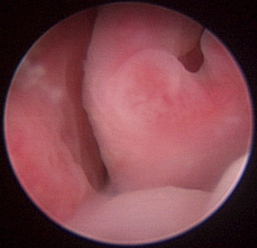

Normal turbinates have a smooth, pink-to-white surface and a spatial alignment that provides channels for the passage of air. The color varies and appears tan in the caudal nasal cavity. Turbinates come in different shapes and sizes, but the surface should be smooth. Ethmoid turbinates in the caudal nasal cavity will have a characteristic stippled or corrugated appearance (Figures 19-13 through 19-16). Ulcerations or various proliferations of the mucosa are indicative of disease. These changes are typically diffuse and accompanied by a lot of mucus. Mucus can be thin to purulent. Copious amounts can be flushed out of the nasal cavity to allow better visibility. The specific disease is determined by biopsy. After full examination of the nasal cavity, run the scope along the floor of the nasal sinus to the level of the choanae. Keeping the scope pointed in a ventral medial direction prevents inadvertent trauma or penetration of the cribriform plate. The index finger of the free hand can be used to follow the scope as it moves caudally over the hard palate; the surgeon can then palpate the scope through the soft palate when it moves into the nasopharynx. Some force is needed to complete this procedure and may result in increased bleeding.

Figure 19-14 Normal canine meatus division.

image